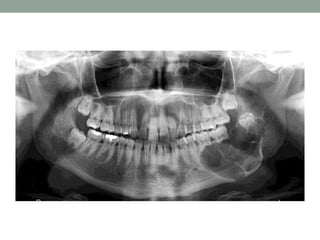

• Radiography:

OPG was advised which showed, multilocular radiolucency

extending from right rams-angle region to mandibular anterior

region with well defined sclerotic border without roots resorption

and thinning of cortical plates and only few mm of mandibular lower

border remaining.

Investigations • Aspiration ofcystic contents: Showed dirty pus colored fluid, contained shredded and fragmented cells of cystic lining. • Protein analysis: Toller postulated that a protein level of less than 4.0 gm/100ml indicated a diagnosis of OKC. • Radiography: OPG was advised which showed, multilocular radiolucency extending from right rams-angle region to mandibular anterior region with well defined sclerotic border without roots resorption and thinning of cortical plates and only few mm of mandibular lower border remaining.